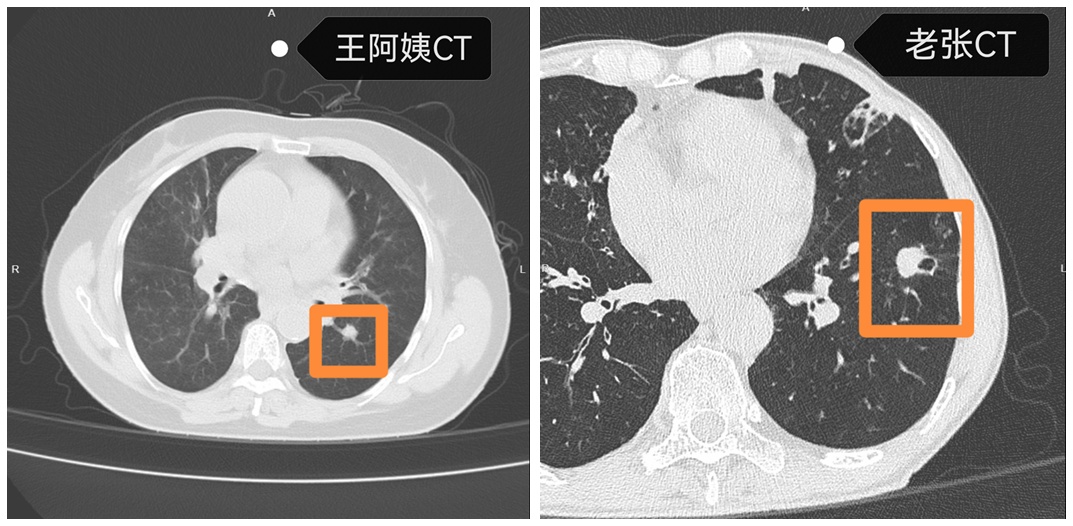

“就像温水煮青蛙,我们都没意识到危险正在逼近。”今年6月,王阿姨因持续发热做胸部CT,意外发现左肺下叶有个直径1.1厘米的实性结节。接诊的鄞州区第二医院心胸外科岑浩锋主任团队迅速行动,通过单孔胸腔镜技术,1小时就完成了肺叶节段切除术。术后确诊为浸润性腺癌,万幸无淋巴结转移。

谁也没料到,这场健康警报还没完全解除。王阿姨出院一周后,陪她来复查的老伴老张,被女儿半是劝说半是强硬地拉着也做了个CT。片子一出来,全家都懵了:老张右肺里,赫然长着个直径约1.9厘米的实性结节。

岑浩锋主任团队再次出手,这次手术只用了30分钟。术中病理出来,同样是浸润性癌。如今,老张正一天天好起来,夫妻俩常在病房里念叨:“这关闯过来了,以后可得好好惜命。”